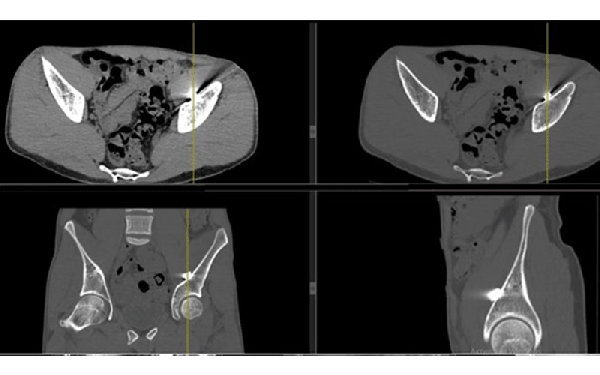

We are not a military hospital, but unfortunately, the number of wounded soldiers is currently so large that military medicine cannot cope with them and numerous civilian hospitals take over the treatment of wounded soldiers. Therefore, among ordinary civilian patients, we examine and treat wounded military personnel. In our hospital, these are mainly acubarotraumas, burns, gunshot wounds of the maxillofacial area, chest, abdominal organs, and of course most of all the trauma extremities.

From the first days we started to provide assistance to wounded civilians and the military from different parts of our country. Our work is to diagnose various injuries of the chest, abdomen, skull, pelvis and especially the limbs. We help thoracic, abdominal and facial surgeons, ophthalmologists, and especially orthopaedists in preoperative and postoperative stages of the treatment.

One of our tasks, as radiologists, has been to find foreign bodies in the people’s arms, legs, abdomen and thoracic wall with help of radiography or ultrasound. We also help in finding traumatic injuries to internal organs. Despite the lack of new equipment, we try to help all our patients as much as possible. Psychological support of patients is also important in our work, which I am doing.